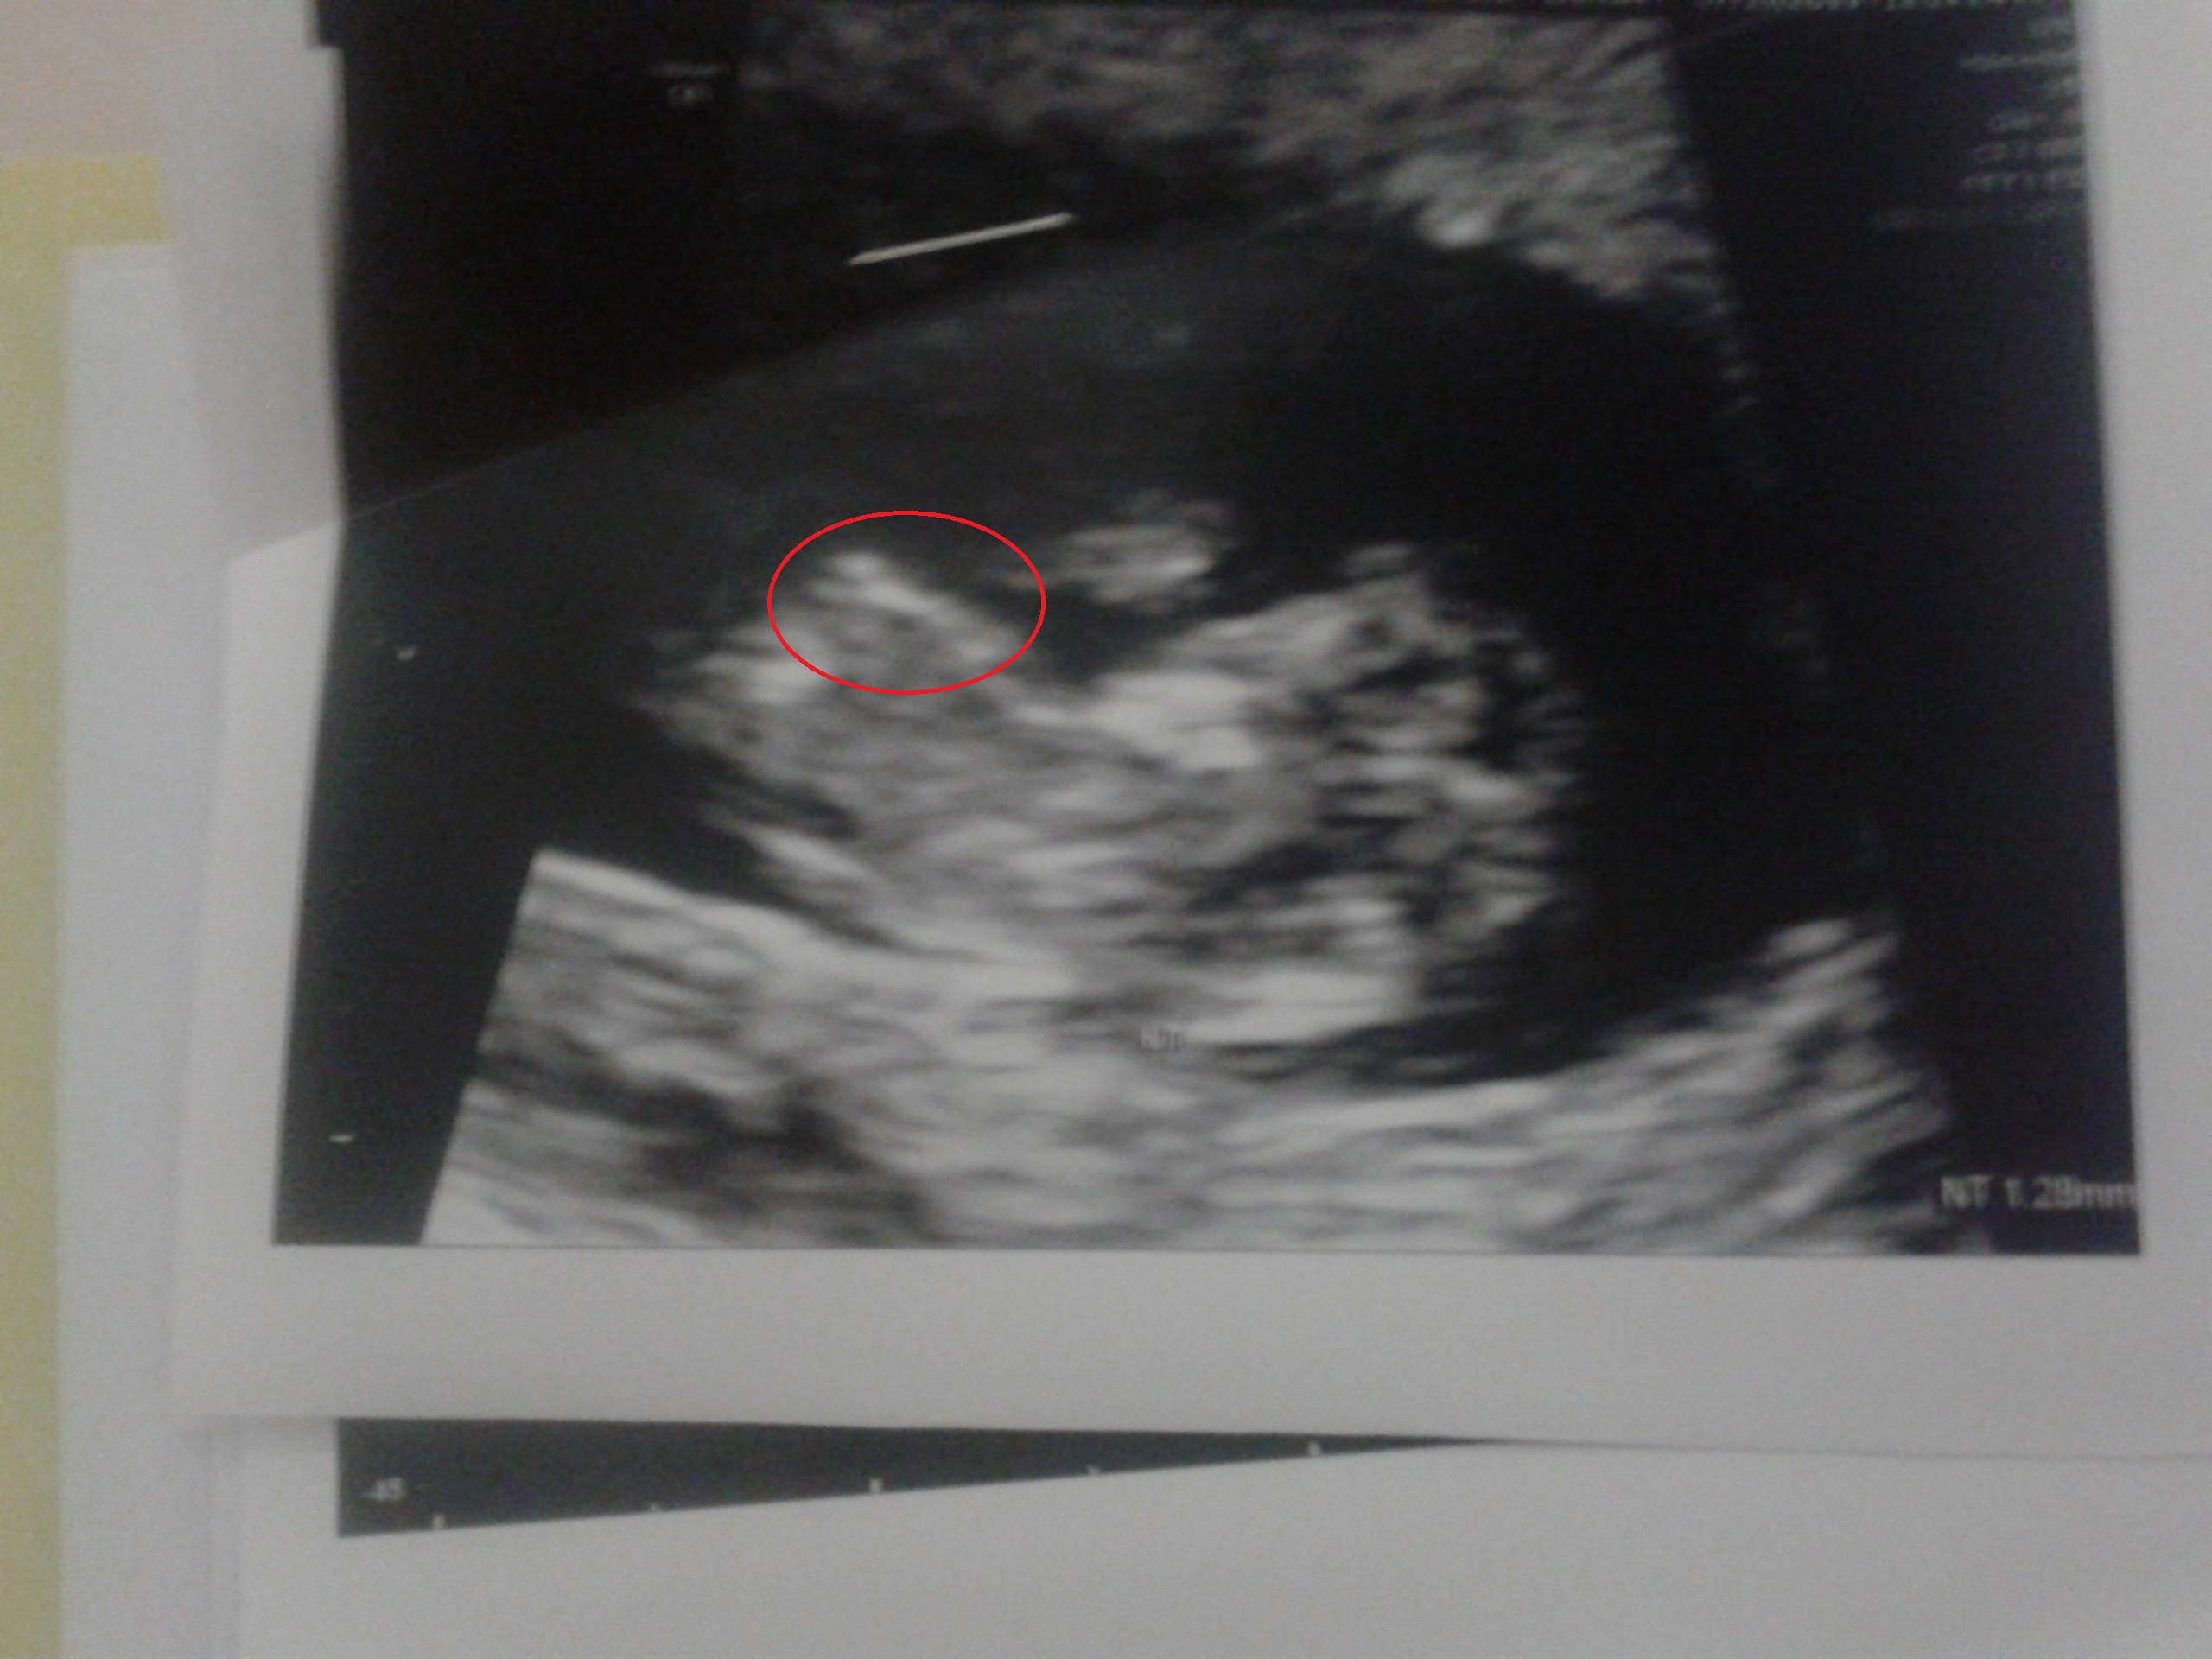

I am 11 weeks along exactly and was pretty bummed to see a forked flat nub thing on my sonogram picture today (I am hoping for a boy). But its position is kind of weird, it is nowhere near where the genitals would be????.Is this even a nub or am I seeing something else like a part of the arm? If it is a nub how did it end up there?Attachment 26210